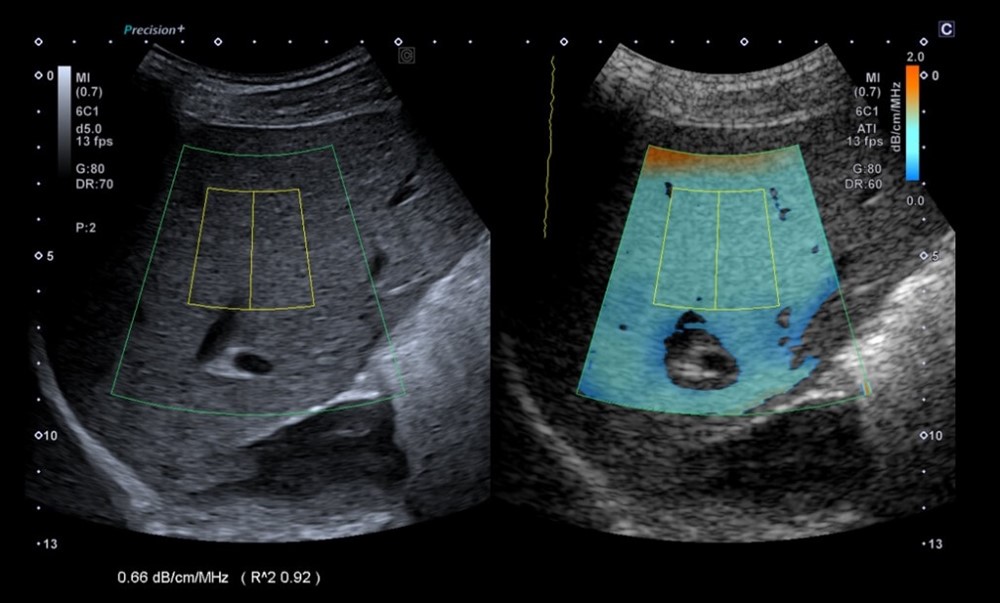

Стеатометрія (ATI – Aplio) – рекомендації для лікаря

1.Що таке стеатометрія (ATI)?

ATI — Attenuation Imaging — ультразвуковий метод кількісної оцінки стеатозу печінки, що вимірює коефіцієнт затухання ультразвукової хвилі (AC — attenuation coefficient, дБ/см/МГц) у печінковій паренхімі.

Чим вищий коефіцієнт затухання → тим більше жиру в тканині.

Метод інтегрований у B-mode, що дозволяє точно обрати ділянку без судин, жовчних протоків та артефактів.

4. Методика виконання

• Виконати якісне B-mode зображення (без тіней від ребер або легені).

• Розташувати ROI на глибині 15–40 мм від капсули печінки.

• Виключити ділянки з артефактами, судинами, протоками.

• Отримати не менше 5 валідних вимірювань, розрахувати середнє.

Система Aplio i900 автоматично відображає значення AC (дБ/см/МГц) та CV (коефіцієнт варіації).

CV ≤0,20 — висока надійність вимірювань.

5. Інтерпретація (за даними досліджень для ATI, Toshiba/Canon Aplio i-series)

• <0,63 дБ/см/МГц — норма або мінімальний стеатоз (S0).

• 0,63–0,69 — легкий стеатоз (S1).

• 0,69–0,72 — помірний стеатоз (S2).

• >0,72 — виражений стеатоз (S3).

Для дітей: норми ще вивчаються; орієнтовно здорові діти мають AC ~0,57–0,62 дБ/см/МГц, але інтерпретацію проводять з урахуванням клініки та біохімії.